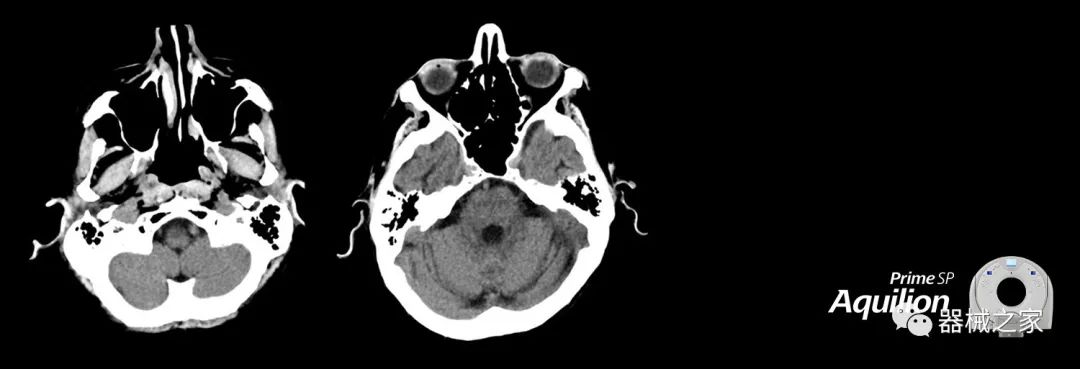

在以患者為中心的放射腫瘤學(xué)領(lǐng)域,計(jì)算機(jī)斷層掃描(CT)的可訪問(wèn)性,可重復(fù)性和靈活性至關(guān)重要。為了建立這些價(jià)值,佳能醫(yī)療系統(tǒng)美國(guó)公司現(xiàn)在正在擴(kuò)大其放射腫瘤學(xué)CT模擬產(chǎn)品,包括Aquilion Prime SP和Aquilion Lightning 80高級(jí)CT系統(tǒng)。除了Aquilion LB之外,Aquilion Prime SP和Aquilion Lightning 80現(xiàn)在還包括放射治療(RT)選項(xiàng),可為腫瘤學(xué)規(guī)劃提供高質(zhì)量的CT成像和精密工具。

Aquilion Prime SP使設(shè)施能夠處理具有挑戰(zhàn)性的案例,同時(shí)為員工提供快速,靈活和高效的解決方案。

佳能醫(yī)療的Aquilion Lightning 80掃描儀還以緊湊,經(jīng)濟(jì)的包裝提供高質(zhì)量的成像。Aquilion Lightning 80旨在可靠,高效地運(yùn)行,在繁忙的環(huán)境中生成高質(zhì)量的圖像。

兩個(gè)CT系統(tǒng)均采用0.5 mm x 80排PUREViSION探測(cè)器技術(shù)(可配置并從80-160現(xiàn)場(chǎng)升級(jí)),78 cm孔徑,50 cm視野,AIDR(自適應(yīng)迭代劑量減少)3-D和SEMAR(單個(gè))能量金屬神器減少)技術(shù)。